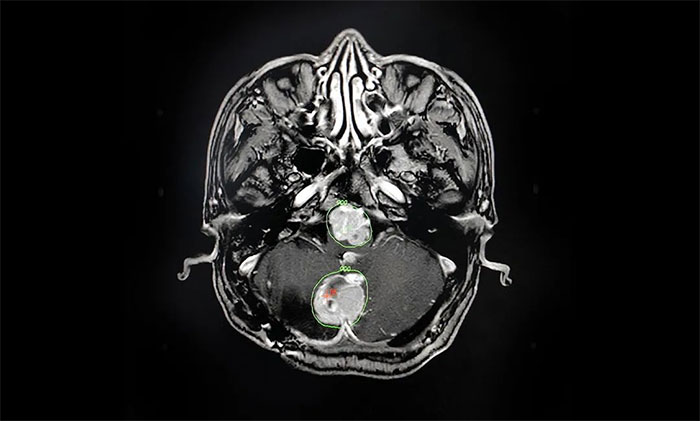

▲ 科学制定伽玛刀治疗计划

▲ 开展头部伽玛刀治疗

经过详细论证,拟定好个性化的治疗方案后,陈琦主任将治疗过程为患者及家属进行了详细说明,并明确告知过程中可能存在的风险。在取得家属一致同意、签字确认后,他立即投入术前的准备工作中。